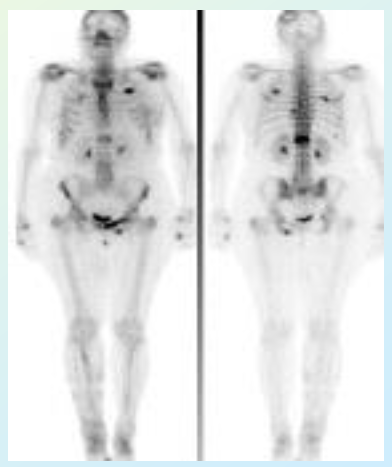

Nucleaire medische beeldvorming

Bij deze techniek wordt een radioactief atoom aan een actieve molecule gekoppeld. Deze molecule gaat naar een specifiek stuk van het lichaam afhankelijk van hoe het lichaam op deze molecule reageert. Het radioactief element die aan deze molecule hangt noemt men een tracer. Het radioactief element vervalt onder natuurlijke vervaltijden. Als men dan de fotonen gaat waarnemen en achterhaalt waar de bron zich bevind, weet men waar de molecule zich bevind. Beeldvormingssystemen die deze techniek gebruiken zijn:

• SPECT = Single Photon Emission CT

• PET = Positron Emission Tomography

Multimodal imaging

Bij multimodal imaging gaat men verschillende technieken combineren in een toestel. Een voorbeeld hiervan is PET/CT waar men zowel functionele als anatomische informatie wilt van het gebied waarin ze geïnteresseerd zijn. Tegenwoordig zijn ze op zoek naar andere technieken die men kan combineren om meer informatie te verkrijgen tijdens één scan.